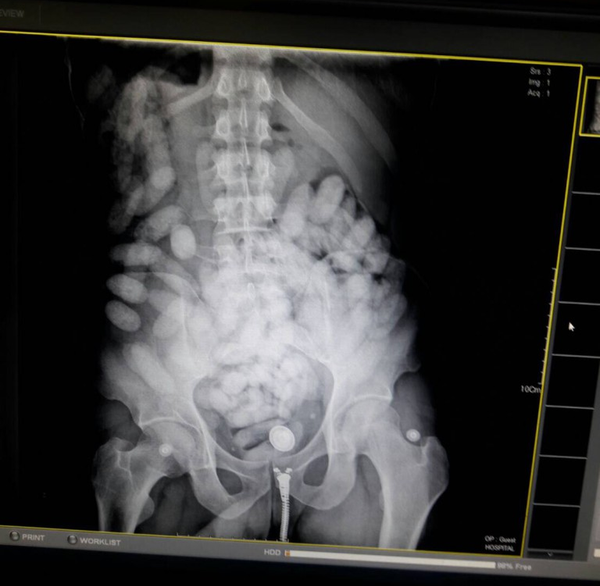

Depois de ter sido submetido a um exame de raio-X, Paulo Henrique Pires do Nascimento foi surpreendido pela a polícia com os papelotes de cocaína escondidos no seu estômago. A droga apreendida pela a polícia foi avaliada em cerca de 6,5 milhões de bats (R$ 605,5 mil).